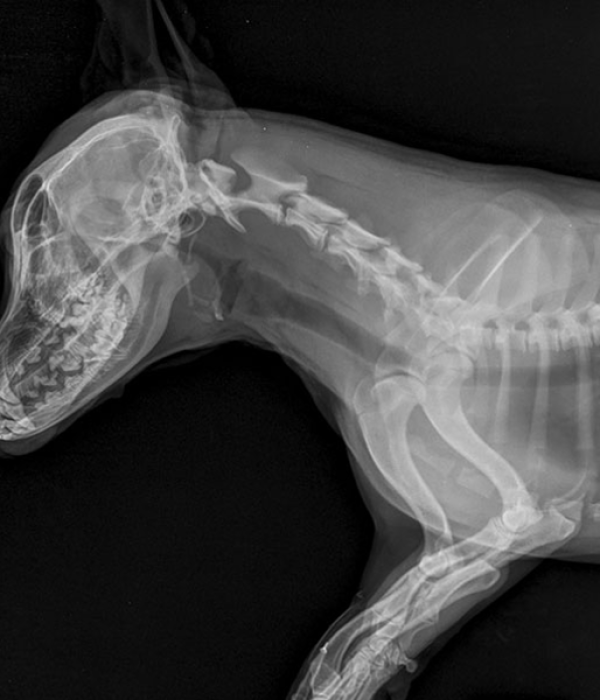

Our hospital is equipped with advanced digital dental and whole-body radiography, as well as ultrasound, to support accurate diagnosis and treatment of a wide range of conditions, including pulmonary, cardiac, gastrointestinal, and urogenital diseases.

Images are immediately available for review by your veterinarian, and for cases that require additional expertise, both radiographs and ultrasound images can be securely sent for interpretation by a board-certified radiologist and AI-powered screening.

Having these advanced imaging tools on-site allows our veterinarians to make faster, more precise diagnoses and develop targeted treatment plans tailored to your pet’s specific needs.